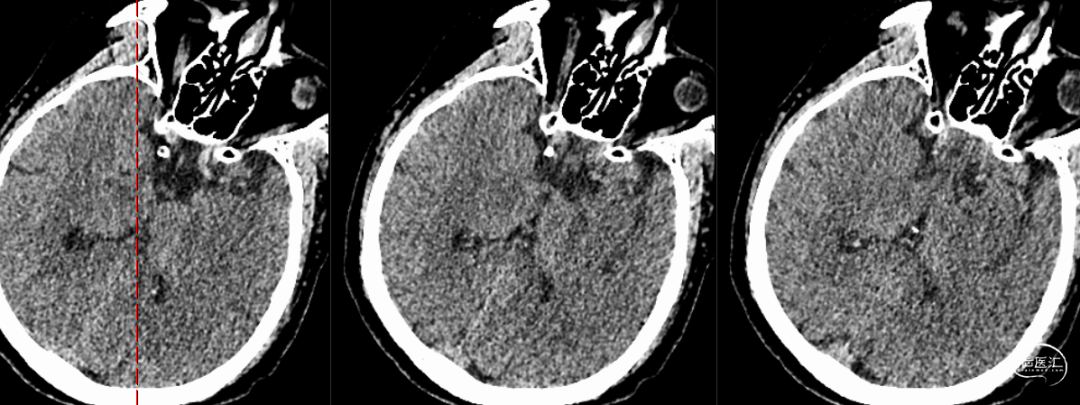

沿微导管送入4.0*30mm Syphonet®取栓支架,造影显示:造影见左侧大脑中动脉M1段约1.8cm细长狭窄显影。大脑中动脉一干仍不显影,考虑狭窄明显并血栓形成。以静脉替罗非班推注12ml,同时静脉7ml/h维持。

沿4.0*30mm Syphonet®取栓支架输送导丝送入2.0*15mm SacSpeed®球囊扩张导管,于大脑中动脉狭窄段缓慢扩张成型后,保留Syphonet®取栓支架造影后提示远端血流改善。5分钟后支架锚定、负压下将6F Tethys®中间导引导管拟送至支架近端并接触血栓(中间导管无法到位),用50ml注射器保持抽吸管负压,回拉Syphonet®取栓支架,取出1枚2.0*2mm细小血栓。

取栓后复查造影见左侧大脑中动脉仍闭塞。

再次将4.0*30mm Syphonet®取栓支架释放到位并造影,见左侧大脑中动脉狭窄段仍明显,且靠近豆纹动脉处。

考虑狭窄明显并夹层形成,遂行4.5*22mm 自膨式闭环支架于左侧大脑中动脉水平段并造影。

最后路径手推造影,造影确认脑血流完全恢复,mTICI 3级。